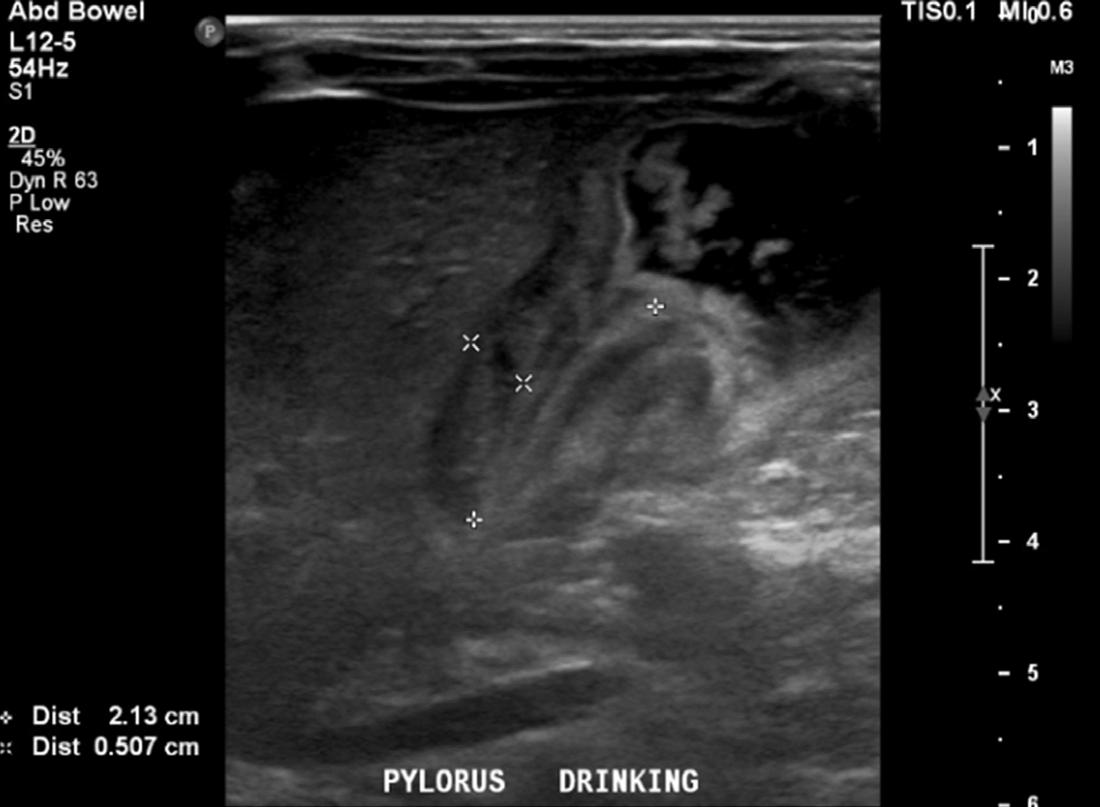

calculate bicarbonate and base excess due to a pH more than 7.70. The patient underwent an abdominal ultrasound in the ED, which suggested IHPS with an enlarged pyloric channel measuring 2.1 cm and a thickened muscle measuring 0.5 cm, again with minimal passage of fluids through the pylorus (Image 1). The surgical team was consulted for the abnormal laboratory and ultrasound findings, but due to the possibility of postoperative edema or residual abnormal external pylorus measurements, the consultant recommended further imaging to conclusively determine pyloric stenosis. The child was admitted for fluid resuscitation and electrolyte replacement. An upper GI series performed the same day confirmed the diagnosis of IHPS when there was lack of contrast passing from the stomach to the duodenum. The patient received a solution of intravenous 5%, dextrose, half normal saline, and 40 mEq potassium chloride at maintenance until electrolytes and intravascular volume

Case Report: An eight-week-old boy with a history of IHPS about six weeks status post pyloromyotomy presented to the ED with vomiting and failure to thrive, and a critically narrowed pylorus was identified by ultrasound. An upper gastrointestinal series confirmed recurrent pyloric stenosis, necessitating another pyloromyotomy.

On further interview with parents and on chart review, the patient was born at term by vaginal delivery with a birth weight of 3,460 grams and a normal physical exam. Six weeks prior, at 17 days of age, he was taken to the ED after two days of persistent, forceful, non-bloody and non-bilious emesis, which occurred after every feed. During that initial ED visit, the patient’s basic metabolic profile was normal, including a potassium of 4.6 milliequivalents per liter (mEq/L) (reference range: 3.7-5.2 mEq/L) and chloride of 103 mEq/L (reference range: 96-106 mEq/L), and an abdominal ultrasound was concerning for an abnormally large pylorus measuring 2 centimeters (cm) in length and 4 millimeters (mm) in width with no passage of food contents. The patient urgently underwent a successful laparoscopic pyloromyotomy without complication. He was discharged home with his parents with